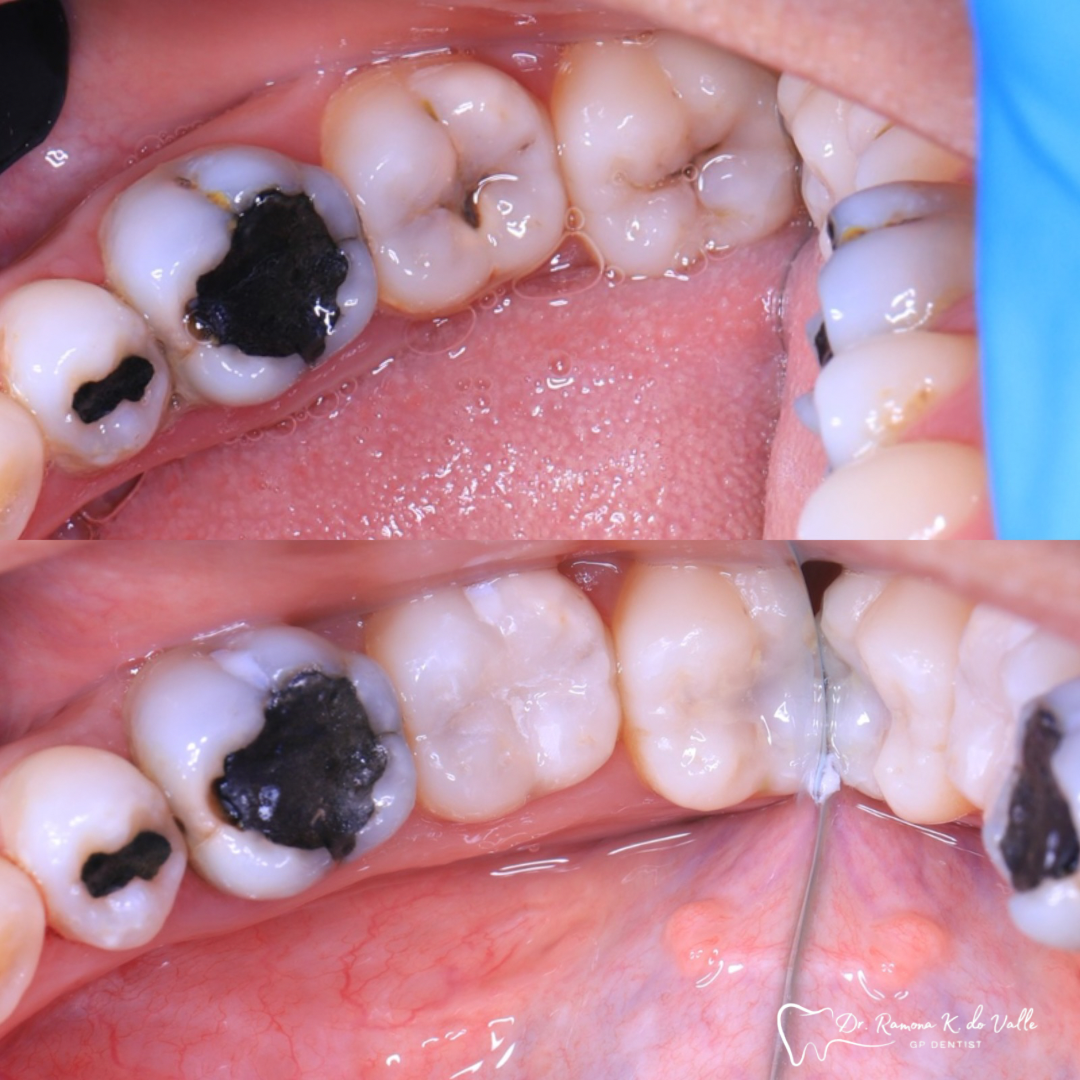

1. Preparation of the Tooth

We remove weakened or decayed tissue and clean the area thoroughly. The goal is to preserve as much healthy structure as possible.

• replacing old metal fillings with a tooth-coloured option